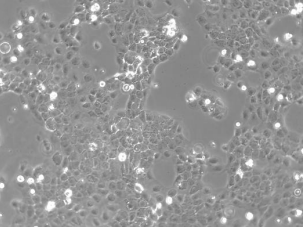

CaSki(人宫颈癌肠转移细胞)

CaSki细胞是从小肠肠系膜转移灶的细胞中建立的。据报道,CaSki细胞含有完整的HPV-16(每个细胞大约600个拷贝)和HPV-18相关序列。

细胞形态

上皮细胞样

细胞类型

肿瘤细胞

生长特性

贴壁细胞